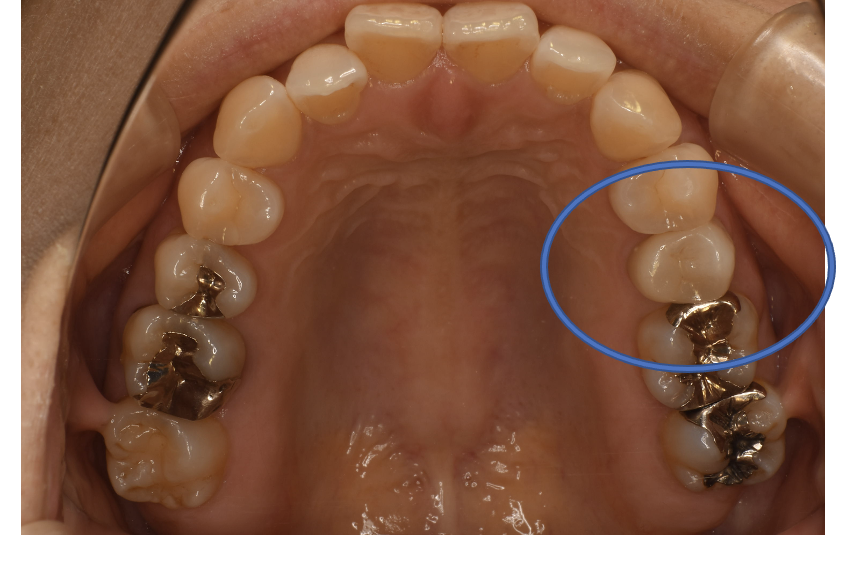

フルジルコニアCr 28 No.72

After

| 治療方法 | フルジルコニアCr 虫歯などで失った歯質を天然歯と同じ色・質感のセラミックの一種であるジルコニア(人工ダイヤモンド)で補う治療法。 |

| 治療のデメリット | 変色がなく耐久性の高い治療ですが、歯周病や二次虫歯を予防するためには歯科医院での定期的なメインテナンスが大切です。 |

| 費用 | ¥89,000×2本=¥178,000 |

| 通院回数 | 1ヶ月〜6ヶ月 |

| 備考 | 院長より 銀歯の内部に虫歯が進行してしまっていたケースです。中を開けて見てみると、外から想像するよりもはるかに虫歯が広がってしまっていました。残存歯質がかなり薄く弱くなってしまったので、ジルコニアで被せて守ってあげています。 |